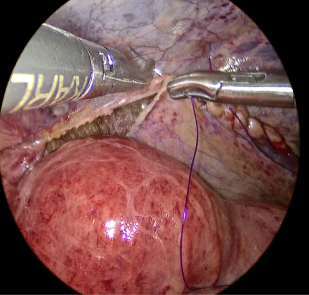

- 腹腔内からヘルニアの部位を観察し、メッシュを用いて補強を行う

メッシュは行う手術によっても異なります。TAPP法では腹腔鏡で行うため、クーゲル法などの従来の方法に対して非常に薄くしなやかなメッシュを用います。来院時に実際のメッシュをご覧いただけます。

- 2ヘルニアの原因となる弱い部分を腹側(内側)からメッシュで補強します。